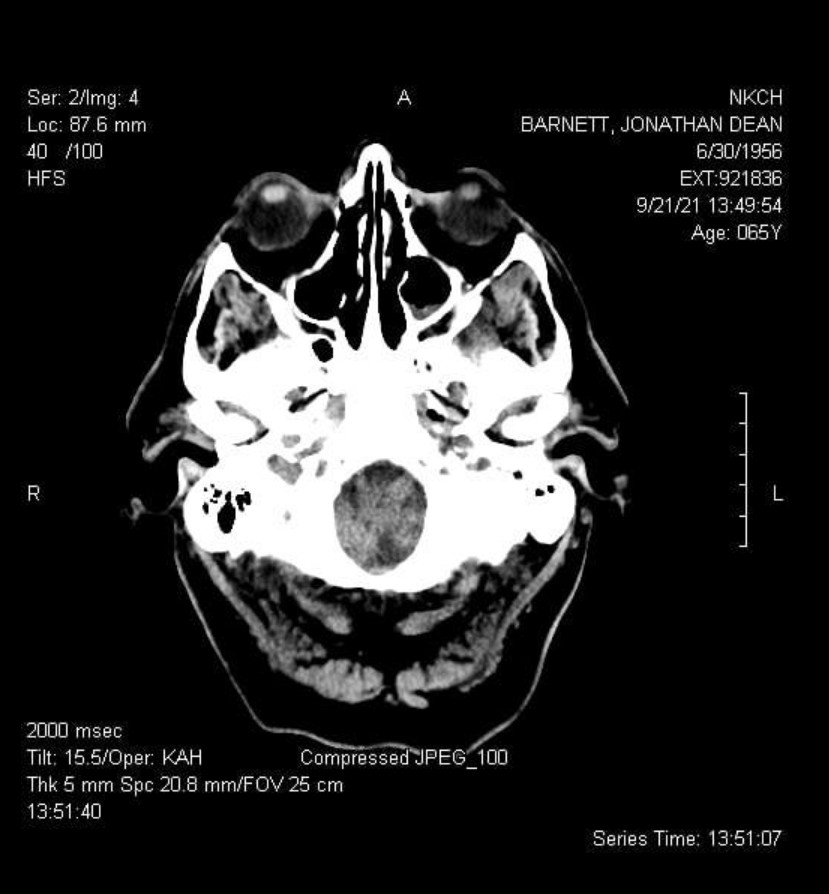

After my left hip replacement in August 2017 (another long and confusticating story), walking wasn’t just exercise. It was reclaimed territory. Independence. Sanity. Proof that I still belonged to my own body. Then came the spinal fusion in June 2023. Another negotiation. Another “you can have function, but you’re going to pay attention now.” Then the coclear implant in my skull, just weeks before leaving the USA for good.

There’s more to this story, of course, and I haven’t yet titled it. There’s no way to talk about pain without talking about the brain. No brain, no pain. It’s not just the body, it’s an integrated living system with so many connections that they can’t all be counted. It’s too easy to get distracted with joints and bones and muscles and tendons and all the rest and forget about the real player in the saga of pain.

The brain.

Chronic pain like this interferes with concentration, planning, and response time. It acts catalytically with the white matter disease (cerebral small vessel disease) that I’ve known about for several years now, amplifying cognitive fog and fatigue. I’ve watched dear friends and close family members live with crippling chronic pain, and I recognize the pattern: pain doesn’t just hurt. It disrupts your life.